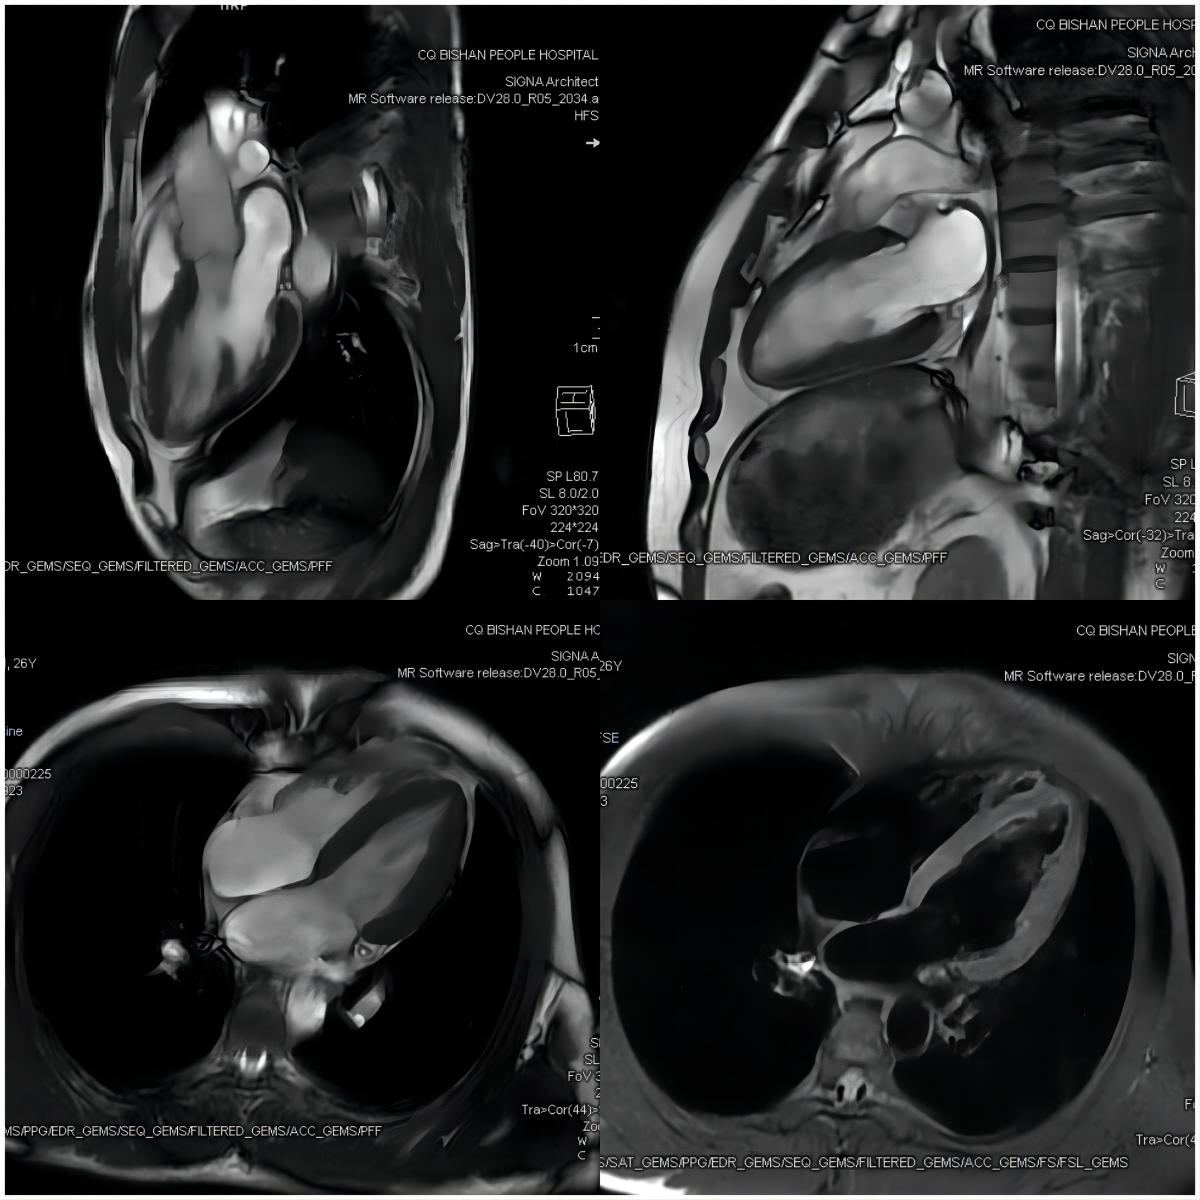

【技術二】心臟磁共振被稱為心臟“一站式檢查”,通過多種掃描序列對心臟進行綜合成像,具有無電離輻射、大視野、任意平面成像等優點,可重復性強,空間、時間和軟組織分辨力良好,還可以實現在體組織“病理影像化”。

【心臟磁共振】